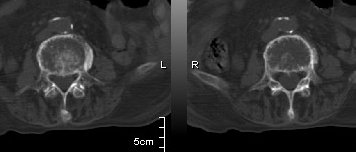

男:89岁因外伤后2天行ct检查。请各位战友讨论图中所指是否是骨折和形成该影像的原因(扫描层面位于椎体中份)。

老年性骨质疏松,椎体前缘出现双边征支持压缩骨折。椎体骨质稀疏,似有破坏,警惕溶骨性骨转移。

椎体前缘双边征,其后椎体内密度增高均提示压缩性骨折

椎体前缘呈双边征 考虑 压缩性骨折,椎体退行性病变。

我的报告1:腰椎骨质退行性改变。

2:t12改变考虑压缩骨折?请结合临床。